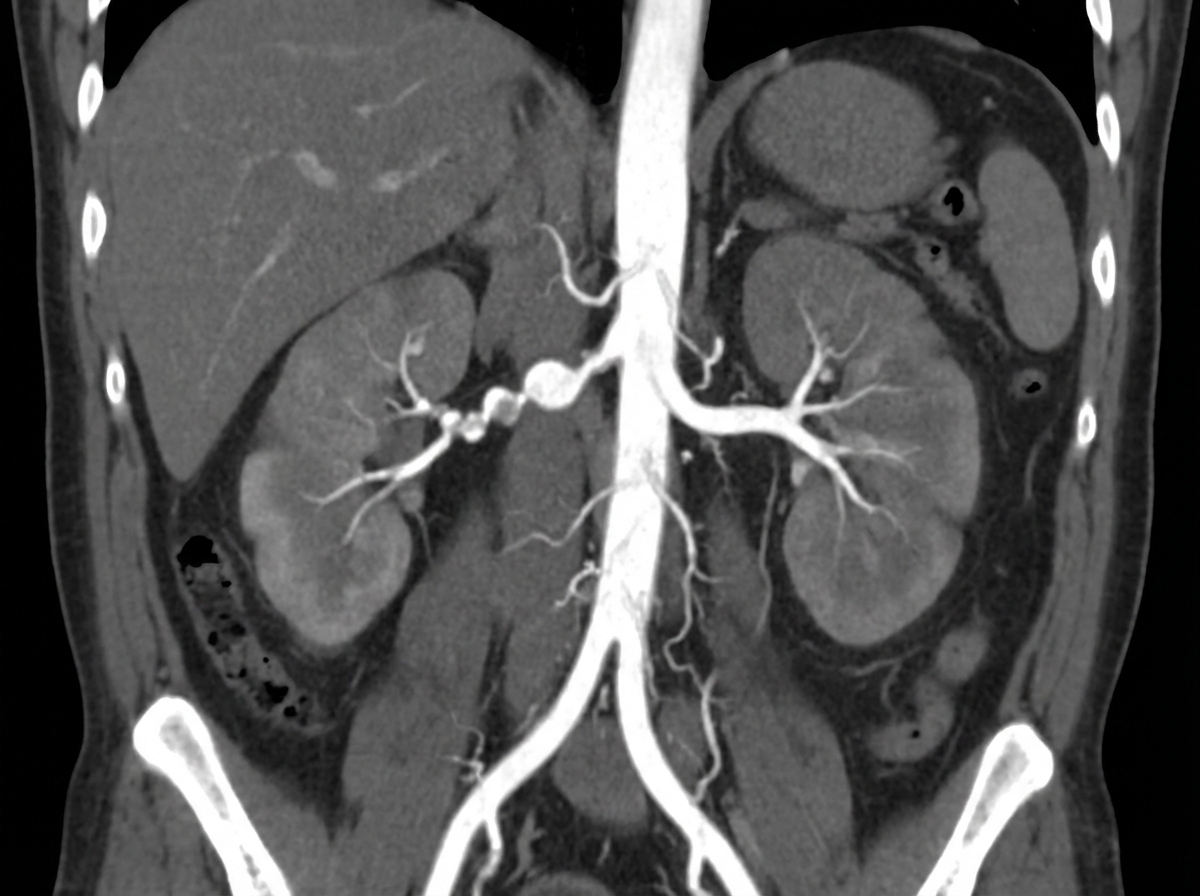

A 26-year-old male presents with abdominal pain and episodes of hematuria. His blood pressure is 160/100 mm Hg and is refractory to standard antihypertensive drugs. Renal Doppler shows a parvus tardus pattern. Subsequent CT renal angiogram was performed. This condition, as depicted, may occur in all of the following except?

Explanation: ***Polyarteritis nodosa (PAN)*** - **PAN** typically causes **microaneurysms** and **necrotizing vasculitis** in medium-sized arteries, not stenotic lesions that would produce **parvus tardus** waveforms. - The **parvus tardus pattern** indicates **proximal renal artery stenosis**, which is not characteristic of PAN's pathophysiology involving aneurysmal dilatation rather than narrowing. *Atherosclerosis* - **Atherosclerotic plaques** commonly cause **renal artery stenosis**, especially at the **ostium**, leading to renovascular hypertension and **parvus tardus** waveforms. - This is the most common cause of **renal artery stenosis** in patients over 50 years, though can occur in younger patients with risk factors. *Fibromuscular dysplasia (FMD)* - **FMD** is a leading cause of **renal artery stenosis** in young adults, particularly women, causing the classic **"string of beads"** appearance on angiography. - The **medial fibroplasia** variant creates alternating areas of stenosis and dilatation, resulting in **parvus tardus** waveforms downstream from the stenotic segments. *Takayasu arteritis* - This **large vessel vasculitis** commonly involves the **renal arteries**, causing stenosis through inflammatory wall thickening and fibrosis. - **Takayasu arteritis** can present with **renovascular hypertension** and **parvus tardus** patterns, particularly in young Asian women with systemic inflammatory symptoms.